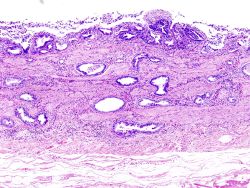

صورة نسيجية تظهر سرطانة غددية في الحويصل الصفراوي

معظم هذه السرطانات من النوع الغدي إلا أن بعضها يكون سرطانة خلايا حرشفية، عادة ما يهاجم السرطان أعضاء الكبد و المعدة والبنكرياس والإثني عشر.